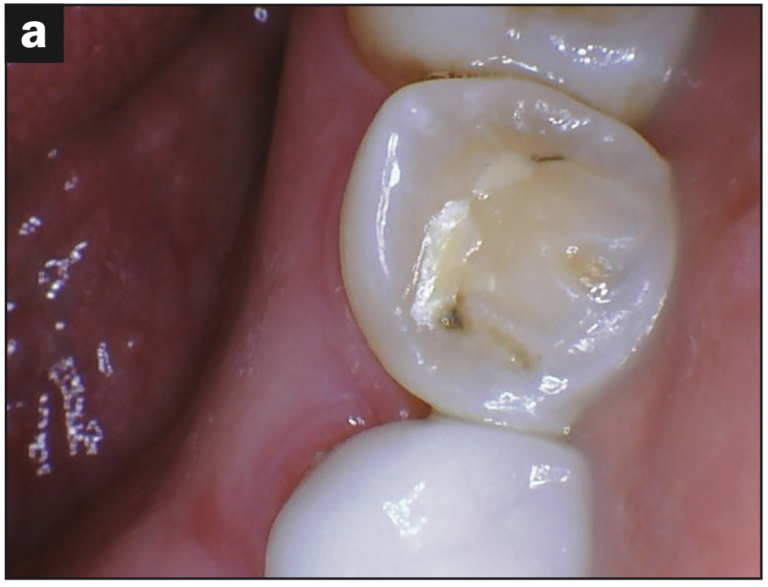

- Abfraction with decay (Figures 2a and 2b)

- Occlusal pitting (Figure 3a)

- Occlusal wear (Figures 3b and 3c)

- Decay (Figures 3b and 3d)